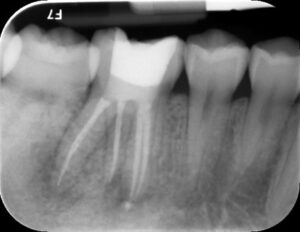

Before and Afters

The tooth will be examined and an x-ray will be taken, a local anaesthetic will be administered. An opening will be made in the crown of the tooth and small instruments will be used to clean the canals. Once the canals have been cleaned and shaped, they will be filled with a polyester synthetic root canal filling and sealer. To make your Root Canal Treatment successful at Notley Dental Care, we will use a dental microscope with magnification so that we get a better view.

Yes, the tooth will require a permanent restoration. This could range from a simple filling to a large build-up with posts and pins. The tooth is more brittle after a Root Canal Treatment and therefore is more susceptible to fracture. If the filling is large, the tooth may need a crown as well. A crown protects the tooth from breaking.